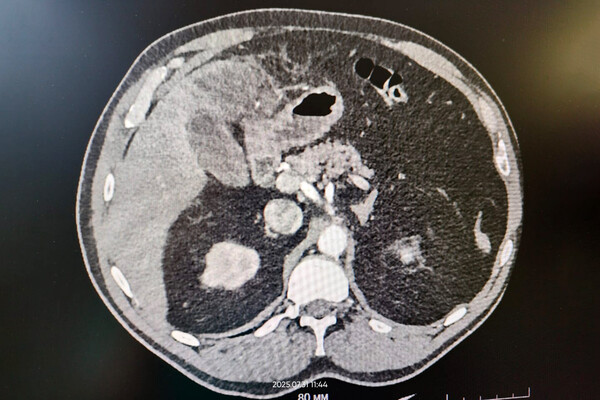

В ходе обследования медики обнаружили, что рыбья кость успела пробить кишечник и застряла в тканях печени. Было принято решение о проведении хирургического вмешательства. Операция прошла успешно, инородное тело удалось извлечь. Спустя трое суток мужчина был выписан на амбулаторное лечение.